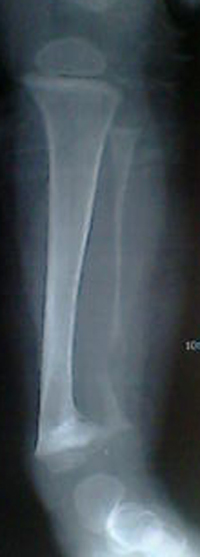

腓骨骨质溶解,大块骨质溶解症可能性大,建议进一步询问病史,进一步检查。有既往片价值更高。

左腓骨呈容骨性破坏。骨皮质及骨髓腔均破坏,下段骨不连续,周围软组织肿胀。考虑骨尤文氏肉瘤可能性大。

腓骨骨质溶解

尤文肉瘤的明显软组织肿块与较小骨质破坏不成比例,本例似乎不符合。应考虑腓骨骨质溶解,建议询问家族史。